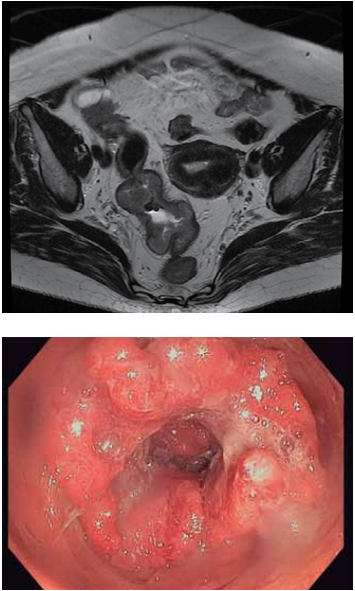

Mulher, 70 anos, DM tipo 2 e HAS, ambas com controle adequado. Hematoquezia há 3 meses. Refere emagrecimento não intencional de 10 kg, em 6 meses. Exames laboratoriais: Hb 10,9 g/dL, plaquetas 220 mil/uL,

Cr 0,95mg/dL, INR 1,0, R 0,95, PCR 15,2 mg/dL, ferritina 40 ng/mL, saturação de transferrina 12%, albumina

3,5 g/dL. Exames de estadiamento negativo para metástases. Realizados os exames diagnósticos a seguir.

(Arquivo pessoal; imagens usadas com autorização)

Qual é o diagnóstico e como deve ser feita a condução dessa paciente no pré-operatório?